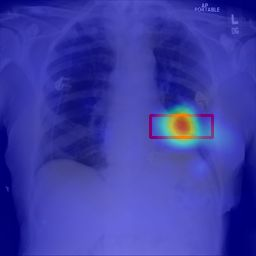

Deployments of artificial intelligence in medical diagnostics mandate not just accuracy and efficacy but also trust, emphasizing the need for explainability in machine decisions. The recent trend in automated medical image diagnostics leans towards the deployment of Transformer-based architectures, credited to their impressive capabilities. Since the self-attention feature of transformers contributes towards identifying crucial regions during the classification process, they enhance the trustability of the methods. However, the complex intricacies of these attention mechanisms may fall short of effectively pinpointing the regions of interest directly influencing AI decisions. Our research endeavors to innovate a unique attention block that underscores the correlation between 'regions' rather than 'pixels'. To address this challenge, we introduce an innovative system grounded in prototype learning, featuring an advanced self-attention mechanism that goes beyond conventional ad-hoc visual explanation techniques by offering comprehensible visual insights. A combined quantitative and qualitative methodological approach was used to demonstrate the effectiveness of the proposed method on the large-scale NIH chest X-ray dataset. Experimental results showed that our proposed method offers a promising direction for explainability, which can lead to the development of more trustable systems, which can facilitate easier and rapid adoption of such technology into routine clinics. The code is available at www.github.com/NUBagcilab/r2r_proto.